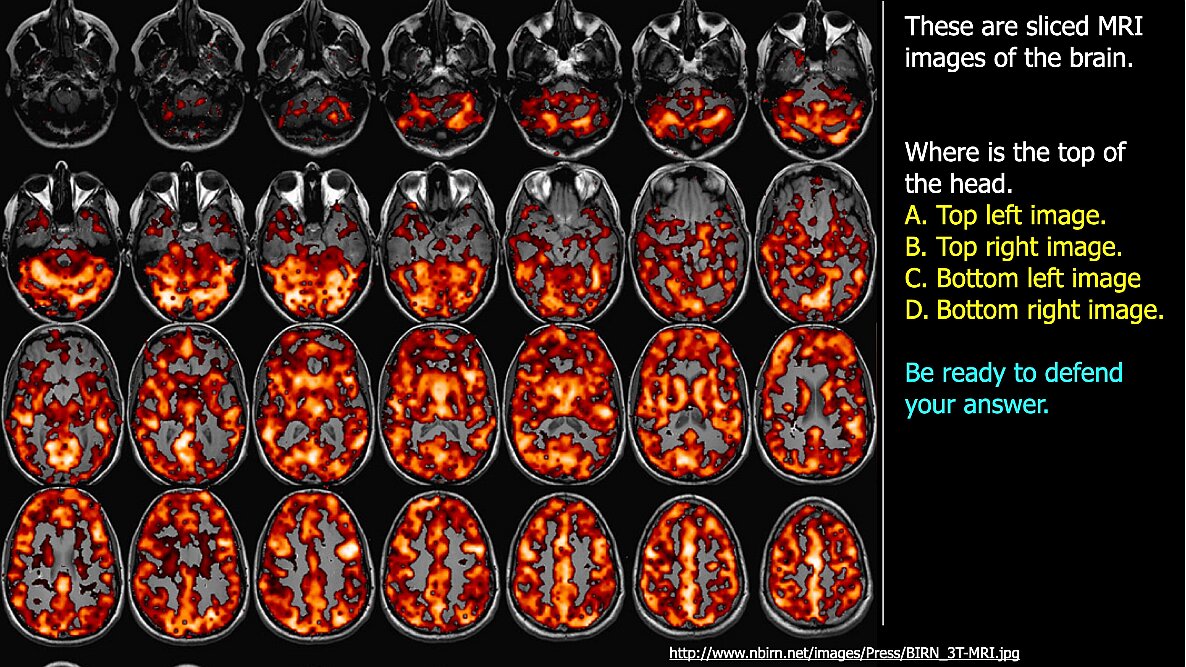

01_5_EandM.033.jpeg 01_5_EandM.034.jpeg 01_5_EandM.035.jpeg

Previous pageNext page01_5_EandM.034

01 5 EandM.034